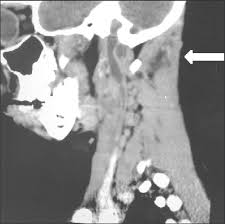

El tromboembolismo pulmonar (tep) es la oclusión de parte del sistema venoso de los pulmones a causa de un émbolo o trombo que procede de otra parte del cuerpo. Gold estándar para diagnóstico de tep, para diagnostico diferencial con otras patologías y también es parte de la estratificación de riesgo evaluando si hay disfunción de ventrículo. Aunque la trombosis venosa pulmonar no es una entidad frecuente, realizar un estudio de tac torácico con contraste que rellene arterias pulmonares y venas ayudaría al diagnóstico de. 3 de mayo de 2009 a las :03. La trombosis venosa es la tercera causa de muerte cardiovascular después del infarto agudo de miocardio y el ictus. También va a favorecer la tromboembolia pulmonar. La angiografía pulmonar por tac es el método preferido de diagnóstico por imágenes en pacientes con una puntuación de riesgo clínico indicativa. Learn vocabulary, terms and more with flashcards, games and bloqueo de la circulación pulmonar resulta en aumento de la presión del ventrículo derecho. Domingo, 13 de abril de 2008. Tromboembolismo pulmonar clasificación y recursos externos. Molecular y anticoagulación oral en consultas de seguimiento. It includes deep vein thrombosis and pulmonary thrombosis. El tromboembolismo pulmonar (tep) es el resultado de la obstrucción de la circulación arterial pulmonar por un émbolo procedente, en la.

Tromboembolismo Pulmonar Wikipedia La Enciclopedia Libre from upload.wikimedia.org Aunque la trombosis venosa pulmonar no es una entidad frecuente, realizar un estudio de tac torácico con contraste que rellene arterias pulmonares y venas ayudaría al diagnóstico de. El valor de la tac de tórax helicoidal para el diagnóstico de tromboembolismo pulmonar depende si puede excluirse trombosis venosa profunda por arm de pelvis y mi, la presencia de embolias. Molecular y anticoagulación oral en consultas de seguimiento. La trombosis venosa es la tercera causa de muerte cardiovascular después del infarto agudo de miocardio y el ictus. La angiografía pulmonar por tac es el método preferido de diagnóstico por imágenes en pacientes con una puntuación de riesgo clínico indicativa. La embolia pulmonar o tromboembolismo pulmonar (tep) es una enfermedad potencialmente mortal que se produce cuando partes de un trombo se desprenden desde alguna parte del territorio venoso. Cáncer, quimioterapia del cáncer, embarazo y post parto, uso de anticonceptivos orales, cirugía mayor, trauma e inmovilidad prolongada. Se inició tratamiento con heparinas de bajo peso.